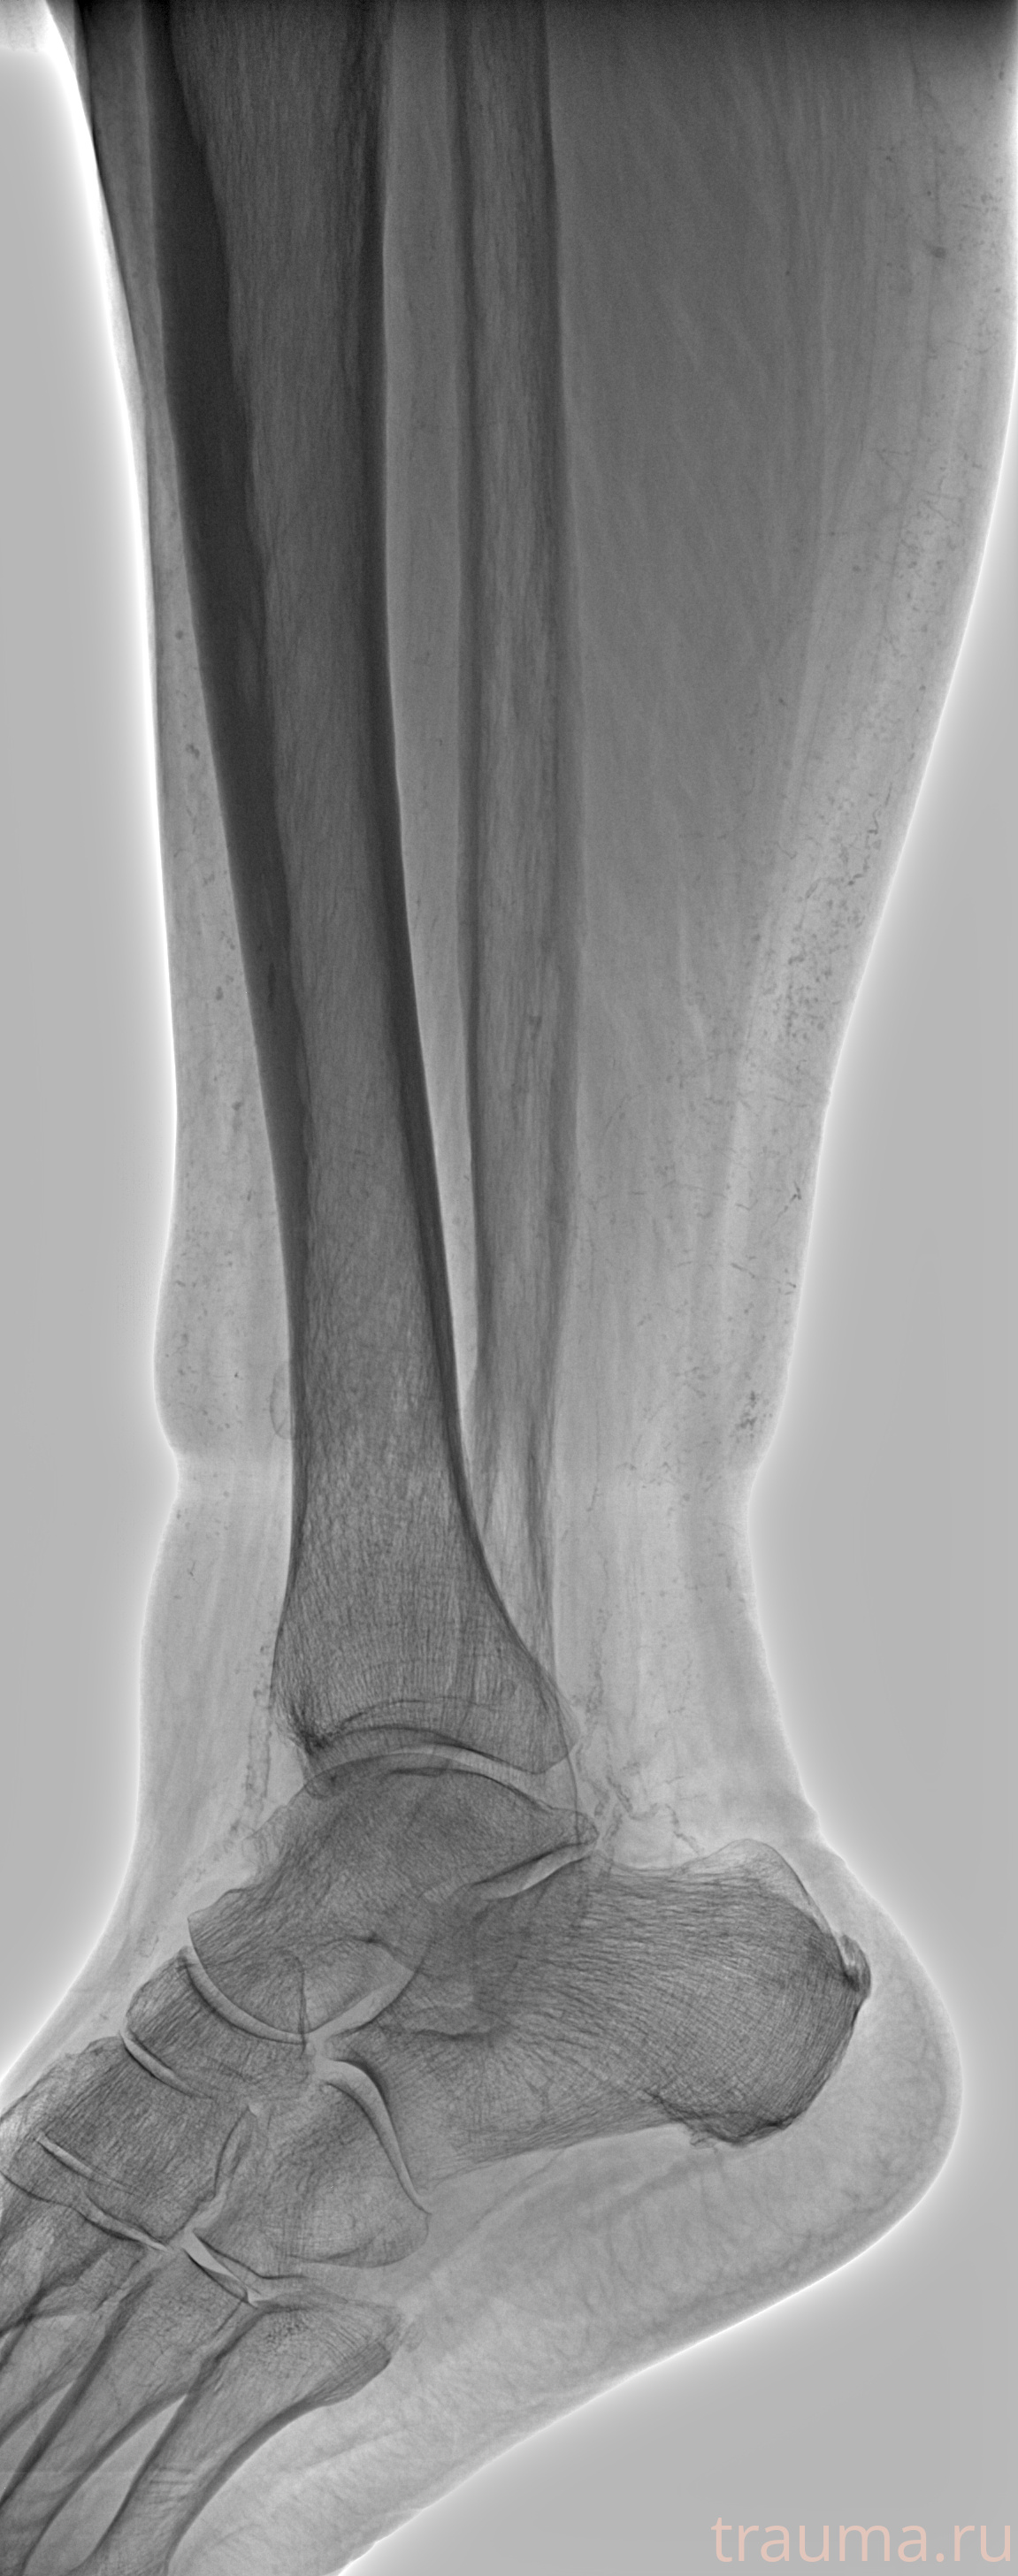

Рентгенограммы

Рентген на дому: по вашему адресу приезжает врач-рентгенолог, травматолог-ортопед с мобильным рентгеновским аппаратом, проводит диагностику травмы или заболевания, делает необходимые рентгенограммы, дает рекомендации по дальнейшему лечению. Получить качественные снимки в домашних условиях возможно благодаря уникальной методике, разработанной МосРентген Центром для института  Склифосовского